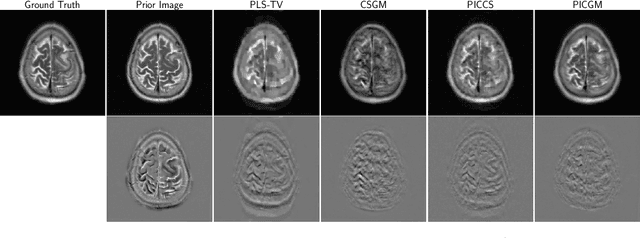

Abstract:Computed medical imaging systems require a computational reconstruction procedure for image formation. In order to recover a useful estimate of the object to-be-imaged when the recorded measurements are incomplete, prior knowledge about the nature of object must be utilized. In order to improve the conditioning of an ill-posed imaging inverse problem, deep learning approaches are being actively investigated for better representing object priors and constraints. This work proposes to use a style-based generative adversarial network (StyleGAN) to constrain an image reconstruction problem in the case where additional information in the form of a prior image of the sought-after object is available. An optimization problem is formulated in the intermediate latent-space of a StyleGAN, that is disentangled with respect to meaningful image attributes or "styles", such as the contrast used in magnetic resonance imaging (MRI). Discrepancy between the sought-after and prior images is measured in the disentangled latent-space, and is used to regularize the inverse problem in the form of constraints on specific styles of the disentangled latent-space. A stylized numerical study inspired by MR imaging is designed, where the sought-after and the prior image are structurally similar, but belong to different contrast mechanisms. The presented numerical studies demonstrate the superiority of the proposed approach as compared to classical approaches in the form of traditional metrics.

Abstract:Obtaining an accurate and reliable estimate of an object from highly incomplete imaging measurements remains a holy grail of imaging science. Deep learning methods have shown promise in learning object priors or constraints to improve the conditioning of an ill-posed imaging inverse problem. In this study, a framework for estimating an object of interest that is semantically related to a known prior image, is proposed. An optimization problem is formulated in the disentangled latent space of a style-based generative model, and semantically meaningful constraints are imposed using the disentangled latent representation of the prior image. Stable recovery from incomplete measurements with the help of a prior image is theoretically analyzed. Numerical experiments demonstrating the superior performance of our approach as compared to related methods are presented.